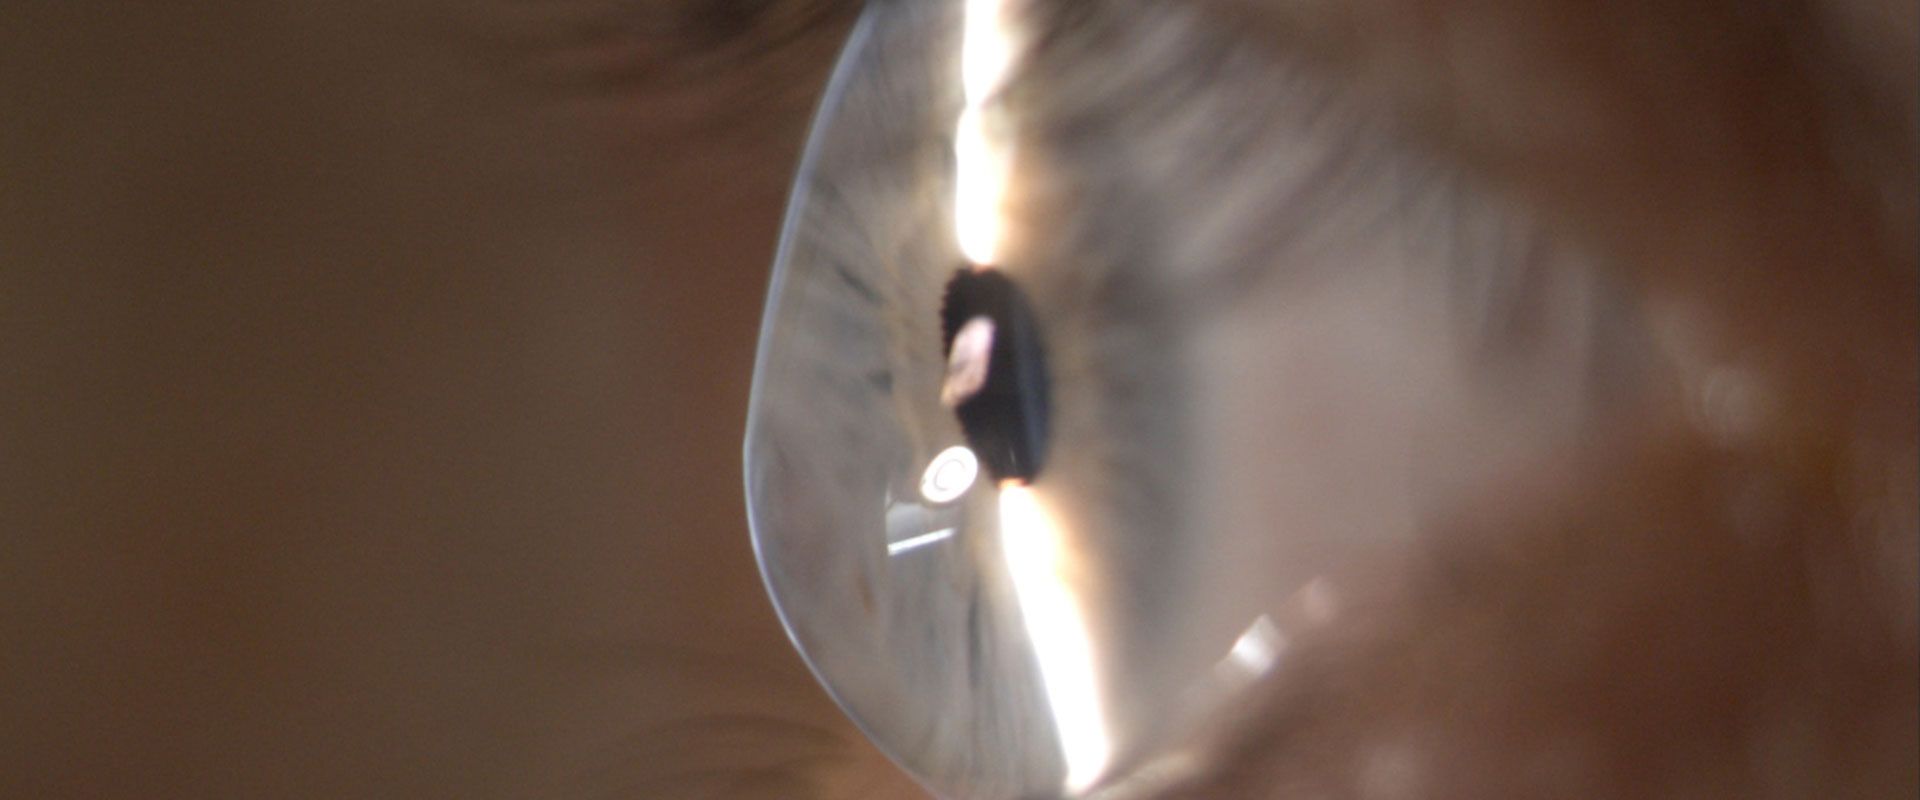

قوز قرنیه وضعیتی از چشم است که در آن قرنیه گرد بهسمت بیرون به شکل مخروطی و برآمده میبشود. قرنیه تکه شفاف و مرکزی سطح جلویی چشم است، از چشم محافظت میکند و علتمیبشود تا دید آشکارتری داشته باشید.

قوز قرنیه (keratoconus) نوعی بیماری چشمی است که در آن قرنیه (قسمت شفاف و گنبدی جلوی چشم) نازکتر و بهمرور زمان به سمت بیرون برآمده میبشود. در این حالت، قرنیه حالت مخروطی به خود میگیرد. با شکل مخروطی این قسمت از چشم، دید چشمها تار و نسبت به نور حساس میبشود. قوز قرنیه طبق معمول هر دو چشم را دچار میکند اما میتواند یک چشم را زیاد تر از چشم دیگر تحت تاثییر قرار بدهد. این بیماری طبق معمول بین اواخر نوجوانی تا ۳۰ سالگی رخ میدهد. احتمالا بتوانید در مرحله های اولیه قوز قرنیه، مشکلات بینایی را با عینک یا لنزهای تماسی نرم اصلاح کنید. با پیشرفت حالت، گمان دارد که ناچار شوید لنزهای تماسی سفت و محکم و قابل نفوذ گاز یا انواع دیگر لنزها همانند لنزهای اسکلرال را منفعت گیری کنید. اگر حالت بدتر بشود، هم نیاز به پیوند قرنیه پیش میآید.